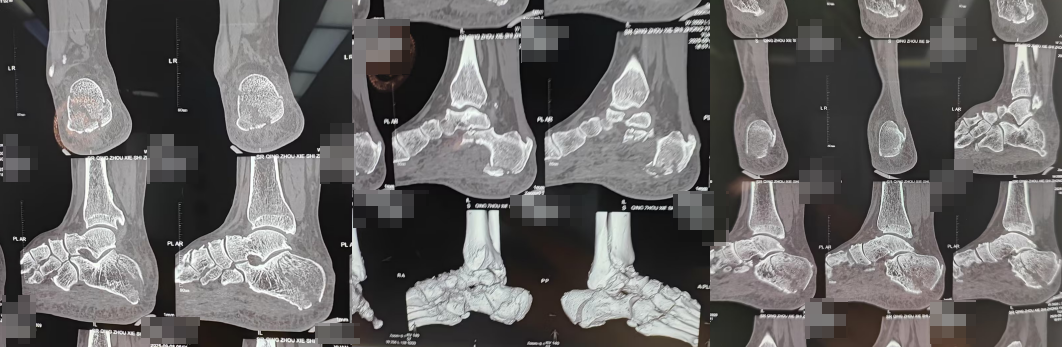

(术前)